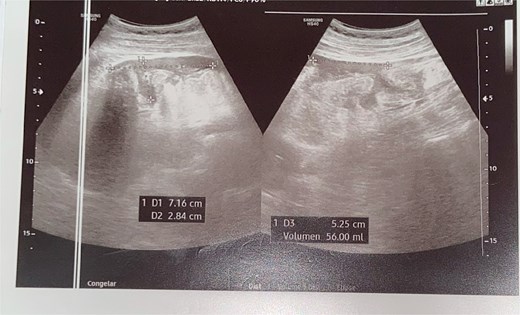

An abdominal ultrasound was performed, as it was the only imaging modality available at the local hospital. The study revealed dilated small bowel loops with a maximum diameter of 7 cm and bowel wall thickness of 2.8 cm, findings consistent with mechanical intestinal obstruction. Free intraperitoneal fluid was estimated at 56 ml. Echogenic tubular structures with parallel lines were observed within the intestinal lumen, and there was focal irregular thickening of the distal ileal wall with punctate hyperechoic foci and reverberation artifacts,suggestive of ileal perforation (Fig. 1). A CT scan was not performed due to limited resources, prompting emergency exploratory laparotomy based on clinical and laboratory findings.

Ultrasound revealing revealed a small amount of free fluid in the perihepatic, perisplenic, and right flank interloop regions.